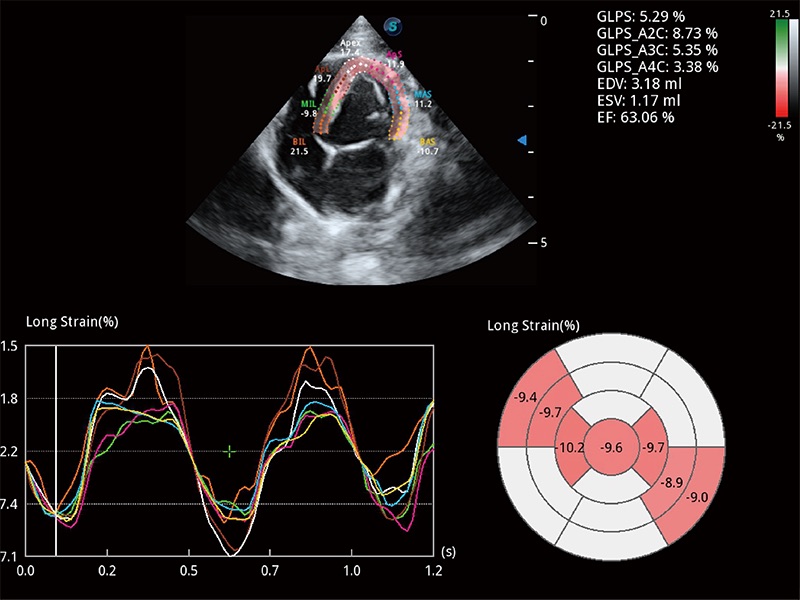

(犬)四腔心MQA

• MQA 心肌定量分析

通过心肌识别技术与二维斑点追踪技术相结合,对心脏的超声图像进行量化分析。计算心肌17个节段的应变、应变率、速度、位移等,并通过牛眼图的形式进行呈现。